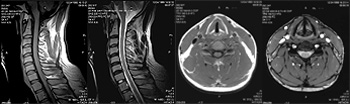

■ 脊髄腔造影

( ミエログラフィー )

脊髄造影検査とは、脊髄のくも膜下腔に造影剤を注入して脊髄、神経根の様子を調べる検査です。  脊髄神経は、背骨の後方の「脊柱管」という骨で囲まれた管の中を通っている細長いチューブのような組織で、周りを「硬膜」と「くも膜」という2枚の膜に包まれています。膜と脊髄の間(くも膜下腔)は「髄液」という液で満たされていて、脊髄神経はこの髄液の中で浮いている状態になっています。この髄液で満ちているくも膜下腔に造影剤を注入して、X 線写真で脊髄本体やそこから枝分かれして出ている神経の枝(神経根)の姿を映し出す検査がミエログラフィーです。 脊髄造影はMRI 検査よりも脊髄神経、神経根の外観を詳細に見ることができます。例えば椎間板ヘルニアがどの神経根をどのあたりで圧迫しているか、脊柱管がどれくらい狭くなっているかなどは MRI よりも分かりやすいです。またCT を同時に撮影して、造影された脊髄の横断面の様子を調べることもあります。